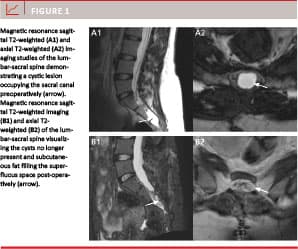

The sacral bone was exposed through a midline incision with the patient in prone position. The posterior wall over the cyst(s) was removed with rongeurs and with careful dissection of the epidural space respecting the cyst(s). Bone chips were preserved. After microsurgical opening of the cyst(s), an attempt was made to identify the CSF fistula. If no CSF fistula could be identified immediately, anti-Trendelenburg posture and modified Quekenstedt maneuver were instituted. In all cases, a fistula was found and a tiny (4-0 or 6-0 vicryl) absorbable tobacco-bag suture encircling the fistula was placed inside the cyst wall, respecting the nerve filaments. The sutured area was covered with a very small piece of muscle and fibrin glue before gentle tightening of the suture. The remaining wall of the cyst(s) was then filled with subcutaneous fat, more fibrin glue was added and the cyst was sutured (Figure 11). The exposed area of dura and the nerve roots were then covered with a double layer of polyanhydroglucuronic acid products and fibrin glue and on top a fair layer of bone chips was replaced in the osseous defect. Finally, fascia, subcutaneous tissues and skin were closed separately with absorbable sutures after final control of haemostasis. No drains were used.

Nineteen (95%) of the 20 cysts were closed and one (5%) was notably diminished at imaging follow-up performed an average of eight (range 1-16) months post-operatively. One patient experienced leakage of blood through the wound during the first few days (case no. 10). No post-operative infections or other complications occurred. One additional patient reported post-operative incontinence for flatulence and faeces during the first two months after the operation after which the symptoms resolved (case no. 8 (Table 3)).